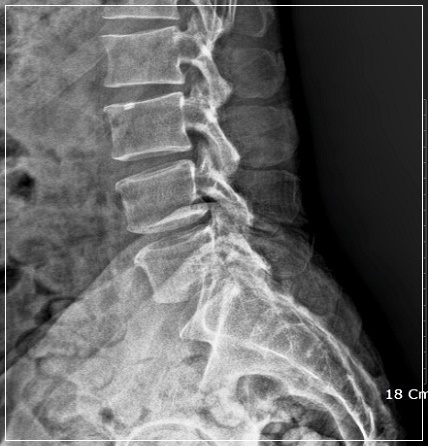

건강보험심사평가원 통계에 따르면, 2017년 척추관협착증 환자 수는 154여만 명에 달합니다. 척추관협착증은 척추 뼈 사이 추간공이 퇴행성 변화 혹은 다른 질환으로 인해 좁아지면서 척추 신경을 눌러 생기는 질환입니다 중년 이후에 많이 나타나는 흔한 질환의 하나로 말 그대로 신경이 지나가는 공간인 척추관이 좁아져서 신경을 누르는 병입니다.

척추관 협착증에서는 주로 뼈, 관절과 같은 딱딱한 조직이 신경을 누릅니다. 통증의 양상을 보면, 허리 디스크는 빠른 시간 내에 진행하는 경우가 많고 척추관 협착증은 오랜 시간에 걸쳐 서서히 나타나는 경우가 많습니다. 또한 척추관 협착증의 특징적인 증상으로 간헐적 파행이 있습니다. 이는 허리 디스크의 증상과 구별되는 것으로 앉아 있을 때는 괜찮은데 조금만 걸어도 다리가 저리고 아파서 앉아 쉬었다가 다시 걸어야 하는 보행 장애 증상을 말합니다.

나이가 들면 누구나 척추관이 조금씩 좁아지게 됩니다. 척추관 협착은 어느 순간 갑자기 일어나는 것은 아닙니다. 척추관 협착증이라는 진단을 받게 되면 병명도 생소하고 어려워 상당히 걱정하게 됩니다. 하지만 허리 디스크와 마찬가지로 척추관 협착증도 일상 생활에 지장이 없다면 수술까지 필요하지는 않습니다.